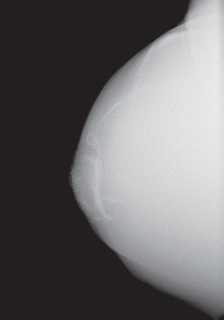

DEFINITION Acetabular bone deficiency may occur primarily (eg, dysplasia, inflammatory arthritis, or seronega…